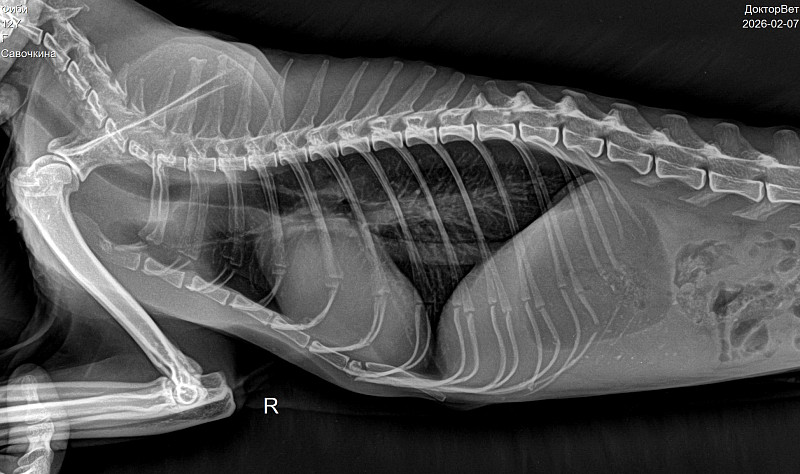

Здравствуйте. Вам нужно провести адекватную оценку ротовой полости. На видео видно, что есть какой то дискомфорт в ротовой полости. Рекомендую вам прием стоматолога. По рентген снимку наблюдается матовость брюшной полости. Рекомендую сделать УЗИ брюшной полости. При почечной недостаточности может быть в том числе уремический стоматит, но это нужно диагностировать визуально и лабораторными тестами